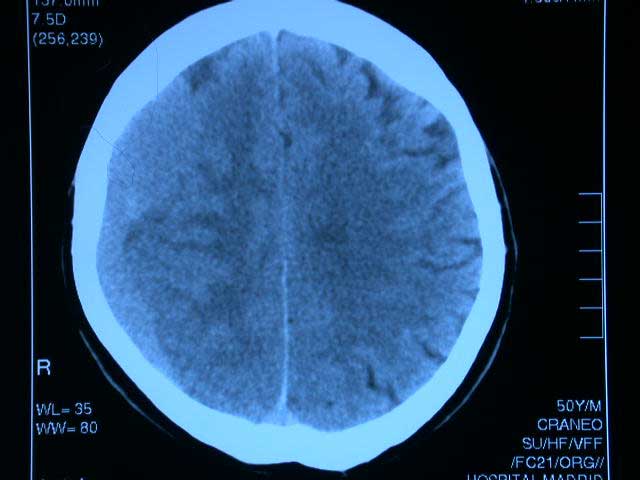

Uso de anticoagulantes y pronóstico de la hemorragia cerebral

25 enero 2018

La mortalidad hospitalaria fue mayor con todos los agentes anticoagulantes, superando el riesgo de la la warfarina al de los anticoagulantes orales directos. JAMA, 25 de enero de 2018